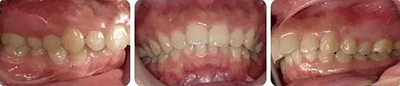

女性,24歲,主訴牙列不齊,面型突。

開唇露齒,閉口時唇肌緊張,反笑線,突面型。

上下牙列輕度擁擠,牙弓偏尖圓形;前牙深覆合深覆蓋;雙側(cè)磨牙尖牙偏遠(yuǎn)中關(guān)系。